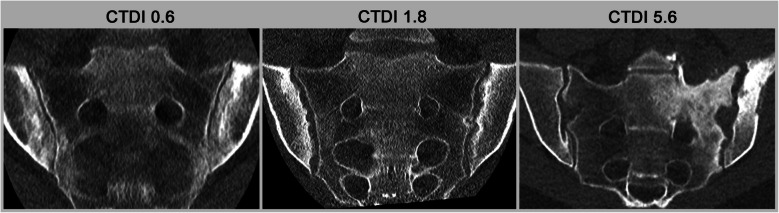

Computed tomography (CT) has traditionally been underutilized in the imaging of inflammatory arthritis due to its limitations in assessing soft tissue inflammation and concerns over radiation exposure. However, recent technological advancements have positioned CT as a more viable imaging modality for arthritis, offering high specificity and sensitivity in detecting structural bone changes. However, advances in ultra-low-dose CT protocols and AI-driven image reconstruction have significantly reduced radiation exposure while maintaining diagnostic quality. Dynamic CT and spectral CT techniques, including dual-energy CT (DECT), have broadened CT's application in assessing dynamic joint instabilities and visualizing inflammatory changes through material-specific imaging. Techniques such as CT subtraction imaging and iodine mapping have enhanced the detection of active soft-tissue inflammation, virtual non-calcium reconstructions, and the detection of bone marrow edema. Possible CT applications span various forms of arthritis, including gout, calcium pyrophosphate deposition disease (CPPD), psoriatic arthritis, and axial spondyloarthritis. Beyond its diagnostic capabilities, CT's ability to provide detailed structural assessment positions is a valuable tool for monitoring disease progression and therapeutic response, particularly in clinical trials. While MRI remains superior for soft tissue evaluation, CT's specificity for bone-related changes and its potential for integration into routine arthritis management warrant further exploration and research. This review explores the current and emerging roles of CT in arthritis diagnostics, with a focus on novel applications and future potential.